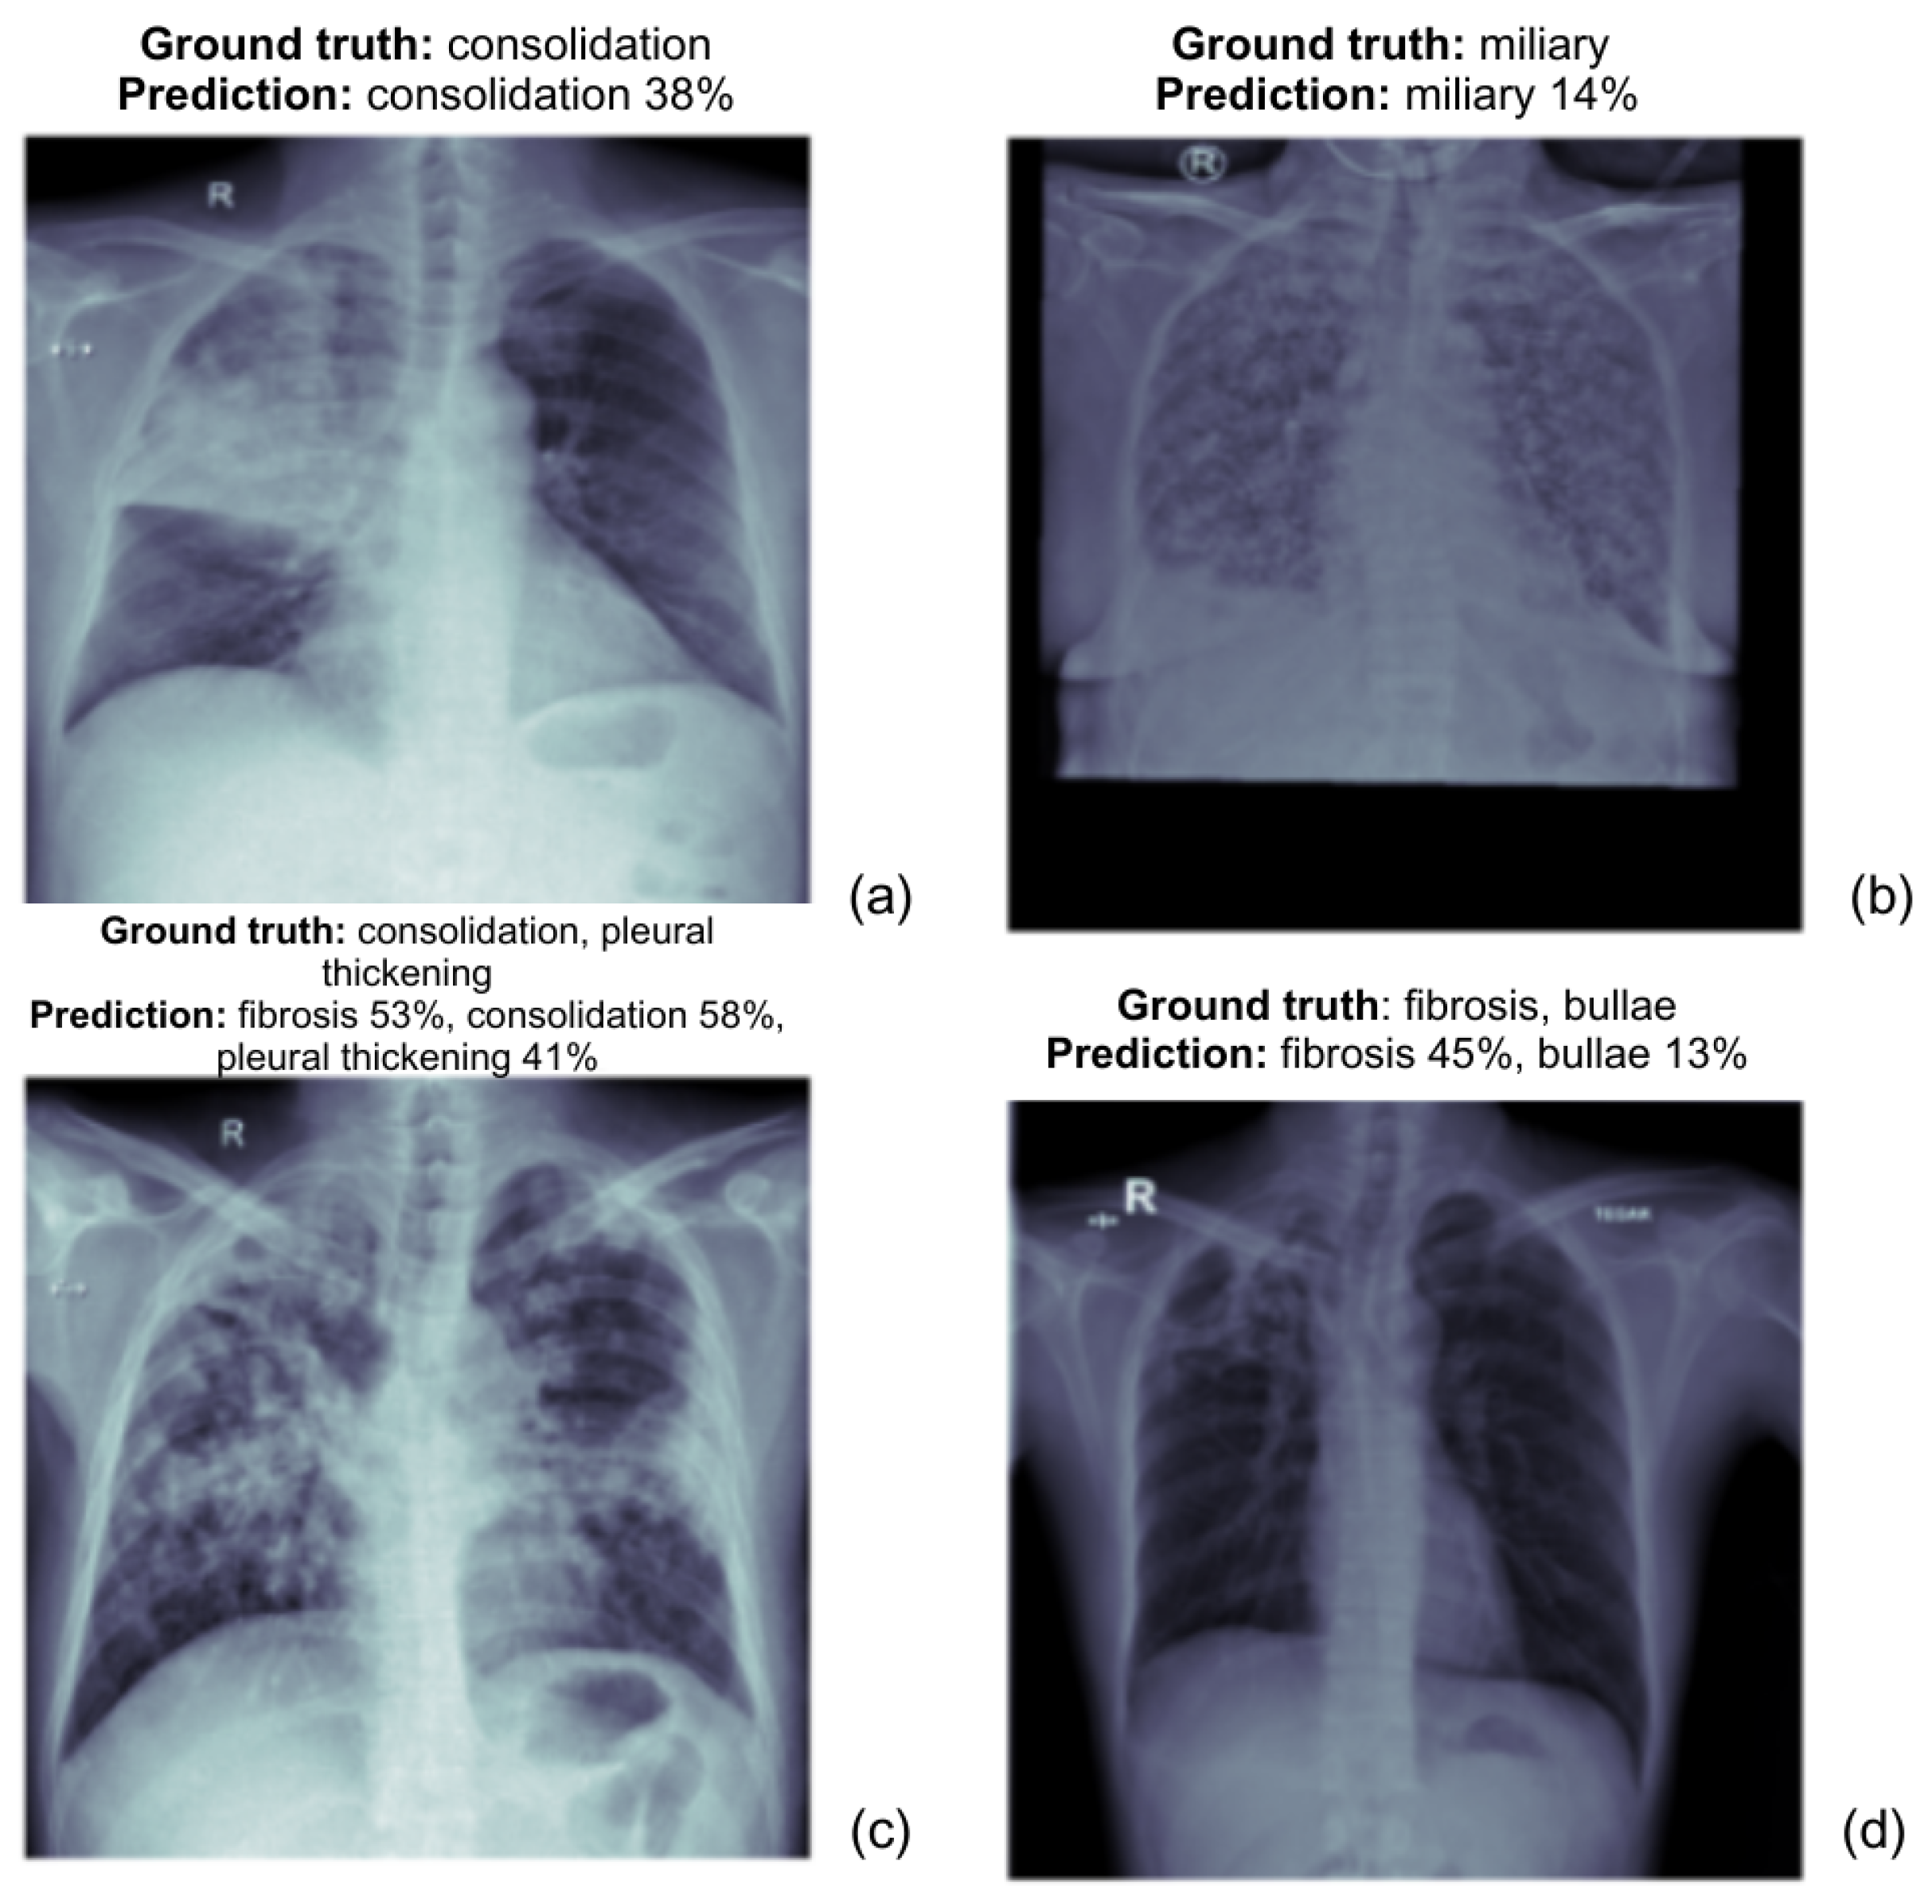

Below, as shown in the Figure 6, are the prediction results of the ViT Base model, demonstrating its ability to classify normal and tuberculosis (TB) anomalies in chest X-rays. Each label is accompanied by a confidence score, highlighting the model’s certainty for each predicted abnormality.

Figure 6.

ViT Base model prediction results for normal and TB anomalies, with confidence score for each label. Each subfigure represents a chest X-ray (CXR) image with the corresponding ground truth and model predictions.

- (a)

- The actual diagnosis is consolidation, and the model predicts it with 38% confidence.

- (b)

- The actual diagnosis is miliary tuberculosis and the model predicts miliary TB with 14% confidence.

- (c)

- The ground truth includes consolidation, fibrosis, and pleural thickening. The model predicts these with fibrosis 53%, consolidation 58%, and pleural thickening 41%, all of which align closely with the actual diagnosis.

- (d)

- The actual diagnosis is fibrosis and bullae, and the model predicts fibrosis with 45% confidence and bullae with 13%. The prediction covers both conditions but is less confident about bullae.